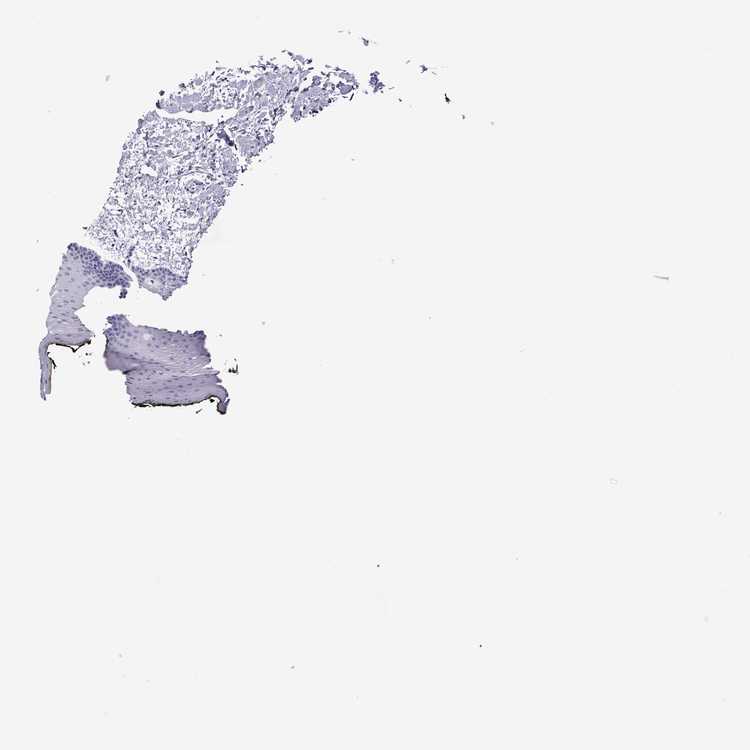

TISSUE PRIMARY DATA ORAL MUCOSA Show tissue menu

ORAL MUCOSA - Antibody stainingi

Antibody staining in the annotated cell types in the current human tissue is reported as not detected, low, medium, or high, based on conventional immunohistochemistry profiling in selected tissues. This score is based on the combination of the staining intensity and fraction of stained cells.

Each image is clickable and will lead to virtual microscopy that enables deeper exploration of all samples and also displays staining intensity scores, fraction scores and subcellular localization as well as patient and tissue information for each sample.

Antibody HPA062278

Squamous epithelial cells Not detected